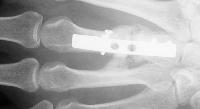

I removed this hardware, and used two mini condylar blade plates at right angles to resecure the distal bone juncture. This allowed more distal purchase while avoiding hardware placement beneath the metacarpal head extensor hood. I replated the proximal bone juncture although it looked clinically healed - not worth taking a chance.

Final result, eight months postop, healed:

Healed.